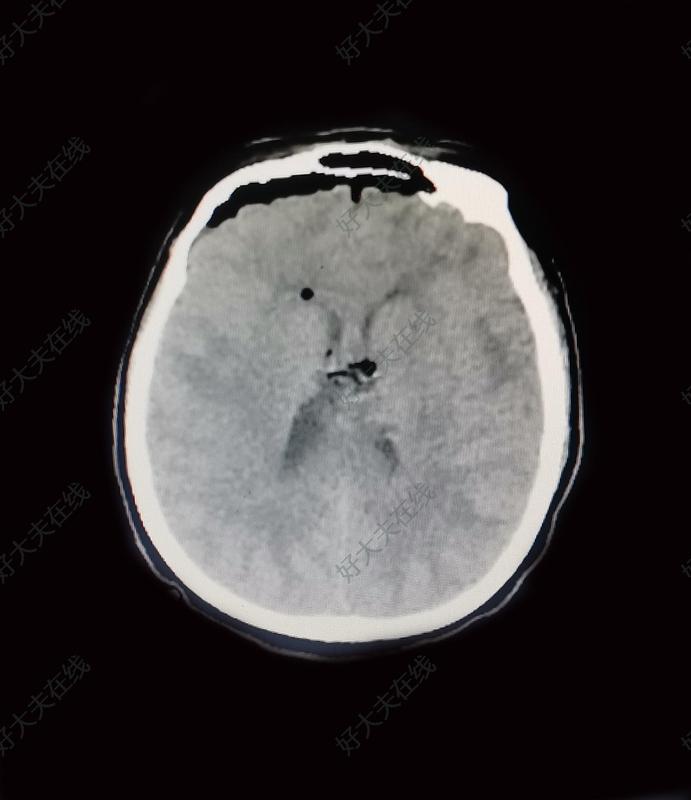

双额叶胼胝体胶质瘤_胶质瘤 - 好大夫在线

图片尺寸800x774